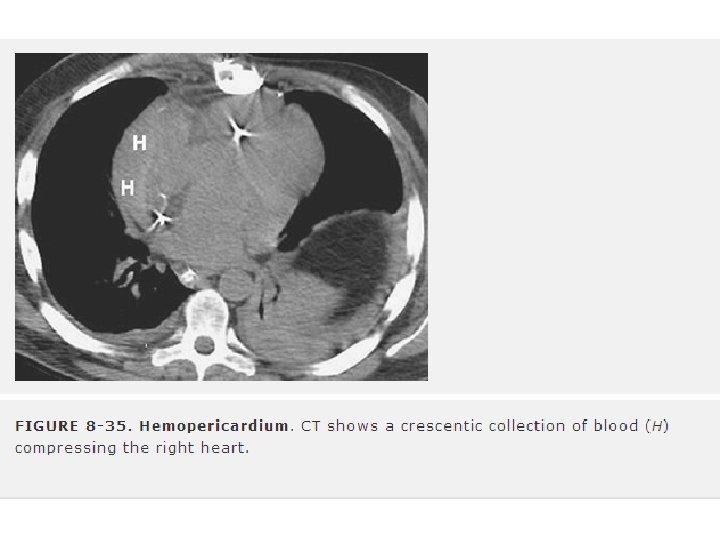

2) KARDİAK TAMPONAD • Penetran yaralanmaların en yaygın sonucudur. • Künt yaralanmalar da neden olabilir. • 15 -20 ml gibi az bir miktar boşaltılması hemodinamik düzelmeyle sonuçlanır. • Beck’s triadı: venöz basıncın yükselmesi, arteriel basıncın azalması ve kalp seslerinin derinden gelmesini içerir. (gürültü + hipovolemi) • Pulsus paradoksus (10 mm. Hg dan fazla)

• Özellikle sol taraftaki tansiyon pnömotoraks kardiak tamponadı taklit edebilir. • Kusmaul işareti (spontan solunumda inspirasyon sırasında venöz basıncın artması) • Nabızsız elektriksel aktivite (hipovolemi ve TPnx) • Transtorasik ekokardiogram, (yanlış negatiflik %5) • Perikardiyosentez (resusitasyona cevap vermeyen kardiyak tamponat olasılığı bulunan hastalarda endike) – subksifoid metod – subksifoid perikardiyal pencere veya torakotomi ve perikardiyotomi – Elektrokardiografik monitör (iğne epikardiyuma değdiğinde T dalgasının voltajı artar).